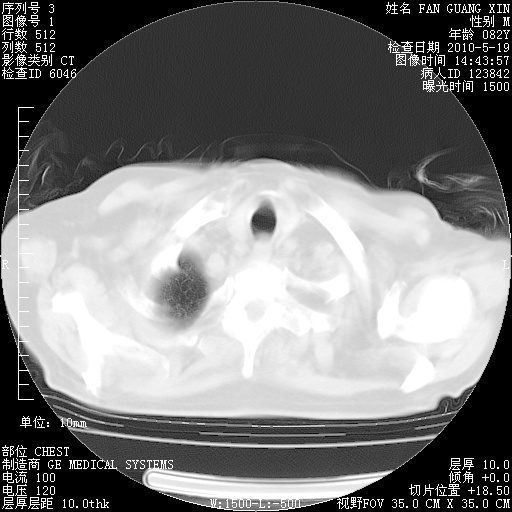

可改为口服强的松40-50mg/d治疗,若病情仍稳定,胸部阴影不再吸收可逐渐减量